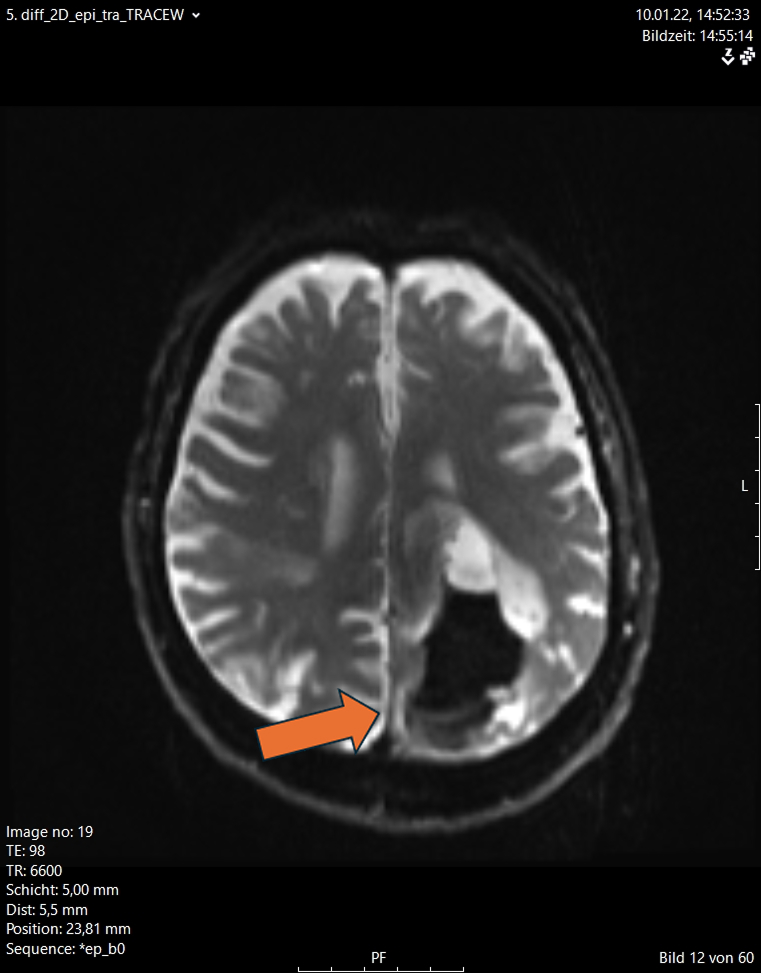

Περισσότερες λεπτομέρειες για τις ενδοεγκεφαλικές αιμορραγίες μπορείτε να διαβάσετε στο αντίστοιχο ενότητα στις παθήσεις (ενδοεγκεφαλικές αιμορραγίες)

Εδώ θέλουμε να τονίσουμε ότι σήμερα είναι δυνατό να αφαιρεθεί μια τέτοια αιμορραγία μόνο μέσω ενός ελάχιστα επεμβατικού ενδοσκοπικού χειρουργείου διάρκειας 20 με 30 λεπτών αντί για τα παραδοσιακά χειρουργεία στα οποία γινόταν μεγάλες κρανιοτομές. Στις εικόνες 12 και 13 απεικονίζονται οι προεγχειρητικές και μετεγχειρητικές εικόνες από δύο ασθενείς με ενδοεγκεφαλική αιμορραγία. Αυτές αφαιρέθηκαν ενδοσκοπικά μέσω μιας απλής κρανιοανάρτησης (1 εκ.)